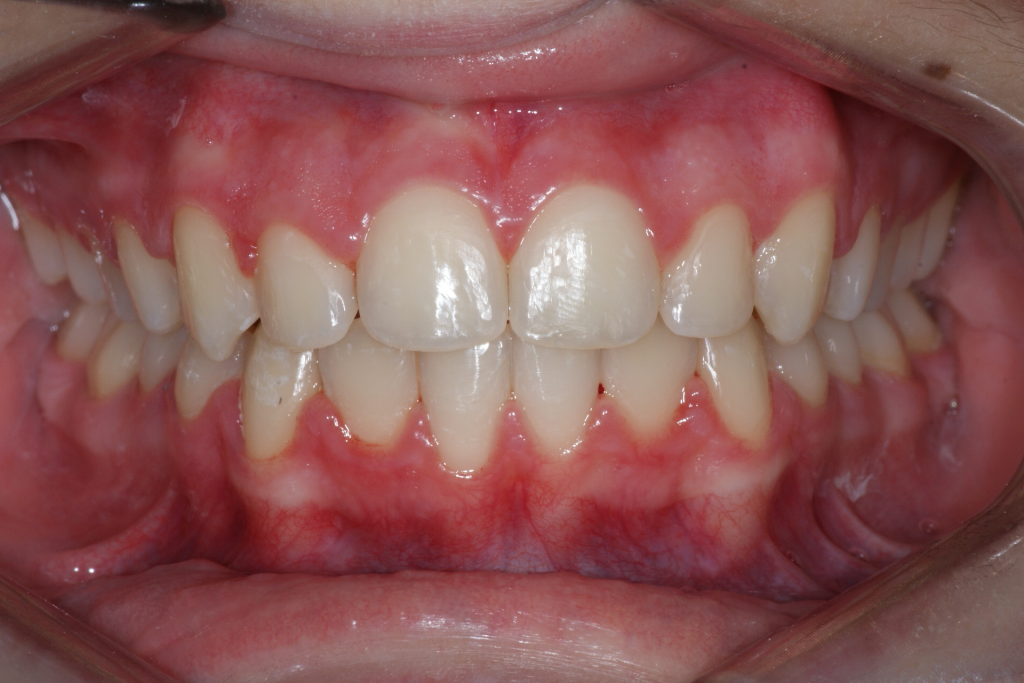

Dans la majorité des cas, un traitement complet est requis afin de corriger la malocclusion et procéder à la traction des canines incluses. Le temps de traitement varie en fonction de l’âge du patient, de la position des canines incluses et de la sévérité de la malocclusion. Ici, nous avons dû procéder à la traction de la canine incluse inférieure droite (#43). La durée du traitement fut de 19 mois, ce qui est exceptionnel puisque habituellement, on parle plus de 24 à 30 mois de traitement pour faire la traction d’une canine.